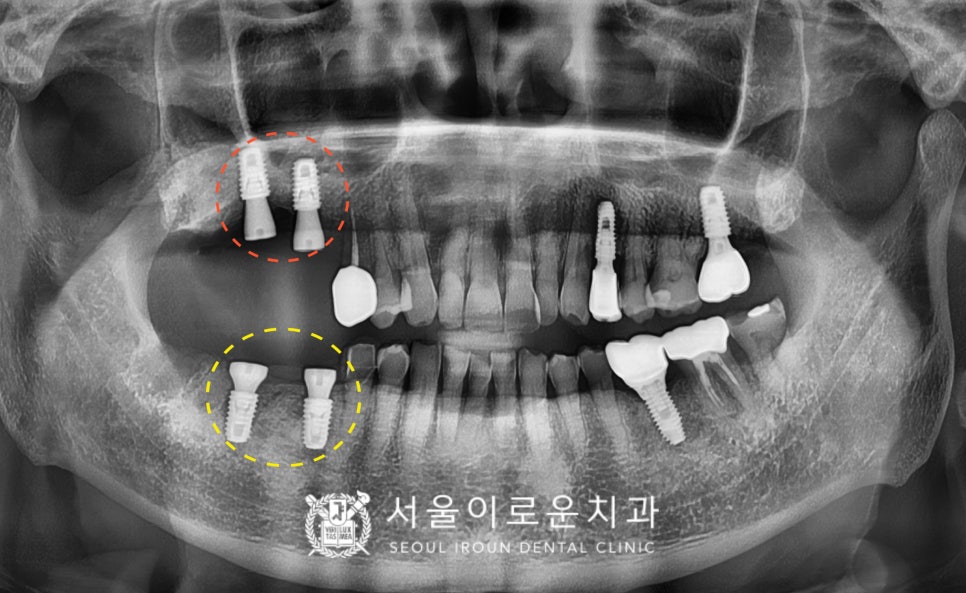

술 후 파노라마와 3D-CT를 통해

발치 후 즉시 임플란트와

상악동 거상술을 동반한 임플란트가

안정적으로 식립된 것을 체크하였답니다.

그리고 위아래 임플란트 식립 후

3~4개월 뒤 osstell beacon이라는

골 유착을 확인할 수 있는 장비를 이용하여

isq 측정하여

뼈와 임플란트가 잘 결합되었는지

안정 값을 확인한 뒤

보철 과정을 진행하였는데요.

그리고 맞춤형 지대주를 체결하고,

자연치아와 강도가 가장 유사하고

심미적인 지르코니아크라운으로

임플란트 보철물을 마무리 해드렸답니다 🙂

임플란트 / 크라운 수복 / 사랑발치를

모두 마무리 한 모습입니다.